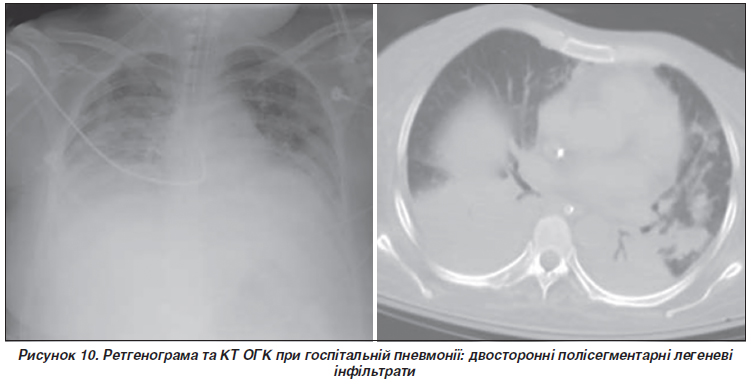

Спектр інфільтративних змін при госпітальній пневмонії широкий і містить вогнищеву, уні- та мультилокулярну інфільтрацію, а також випіт у плевральну порожнину (рис. 10).

Можливе багаторазове контрольне рентгенологічне дослідження, оскільки необхідно не лише виключити ускладнення пневмонії, але й виявити інфільтрати, появу яких передбачити неможливо. На початку захворювання, тобто в першу годину після появи симптомів, у хворих з нейтропенією результати рентгенологічного дослідження можуть бути негативними.